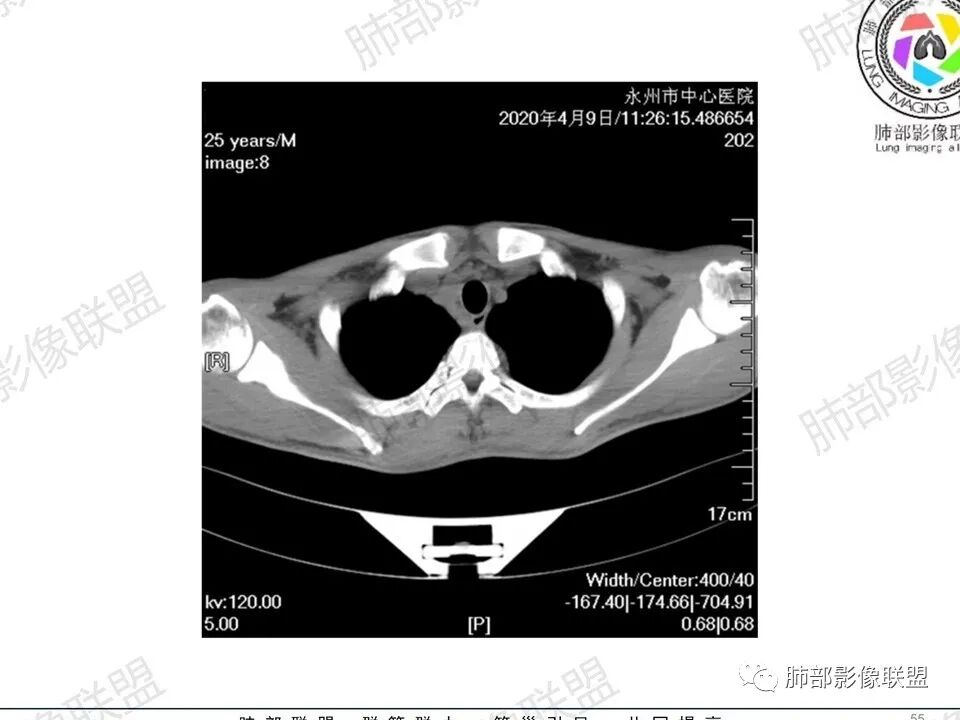

1、临床信息:青年男性,慢性病程,咳嗽气促,伴盗汗胸痛。

2、实验室检查:低色素性贫血,血沉快,铁蛋白明显增高,凝血功能降低,蛋白降低,乙肝表面抗原阳性,叶酸低,CRP 高,白细胞及中性高。

3、影像表现:双肺散在斑片影及结节影,部分结节内可见血管穿行,斑片影沿支气管血管束分布,近胸膜侧病变收缩不明显。部分中央淋巴间质增厚,小叶间隔增厚。病灶内支气管穿行,部分支气管略扩张。局部小结节呈串珠样改变。纵隔、肺门区、锁骨上及腋窝淋淋巴结肿大,部分有融合。心腔低密度。脾大。

1.年轻男性,咳嗽咳痰1年,气促2月,伴胸痛盗汗。长病程。

5.双肺门及纵隔淋巴结显著增大,这改变相当显眼。这里强调“双肺门”及“多发”!

增大的淋巴结密度偏低且均匀。此外患者有体表淋巴结增大。